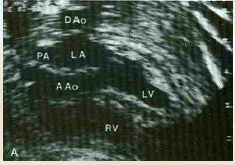

what is speciat about these veiws of the <3 ?

Left Ventricular Outflow Tract – AKA Aortic root or 5-Chamber view

Right Ventricular Outflow Tract

what does the left ventricular outflow tract (LVOT) demonstrate?

continuity of the interventricular septum to the aortic root

what does the rt ventricular outflow tract (RVOT) demonstrate?

Demonstrates main pulmonary artery